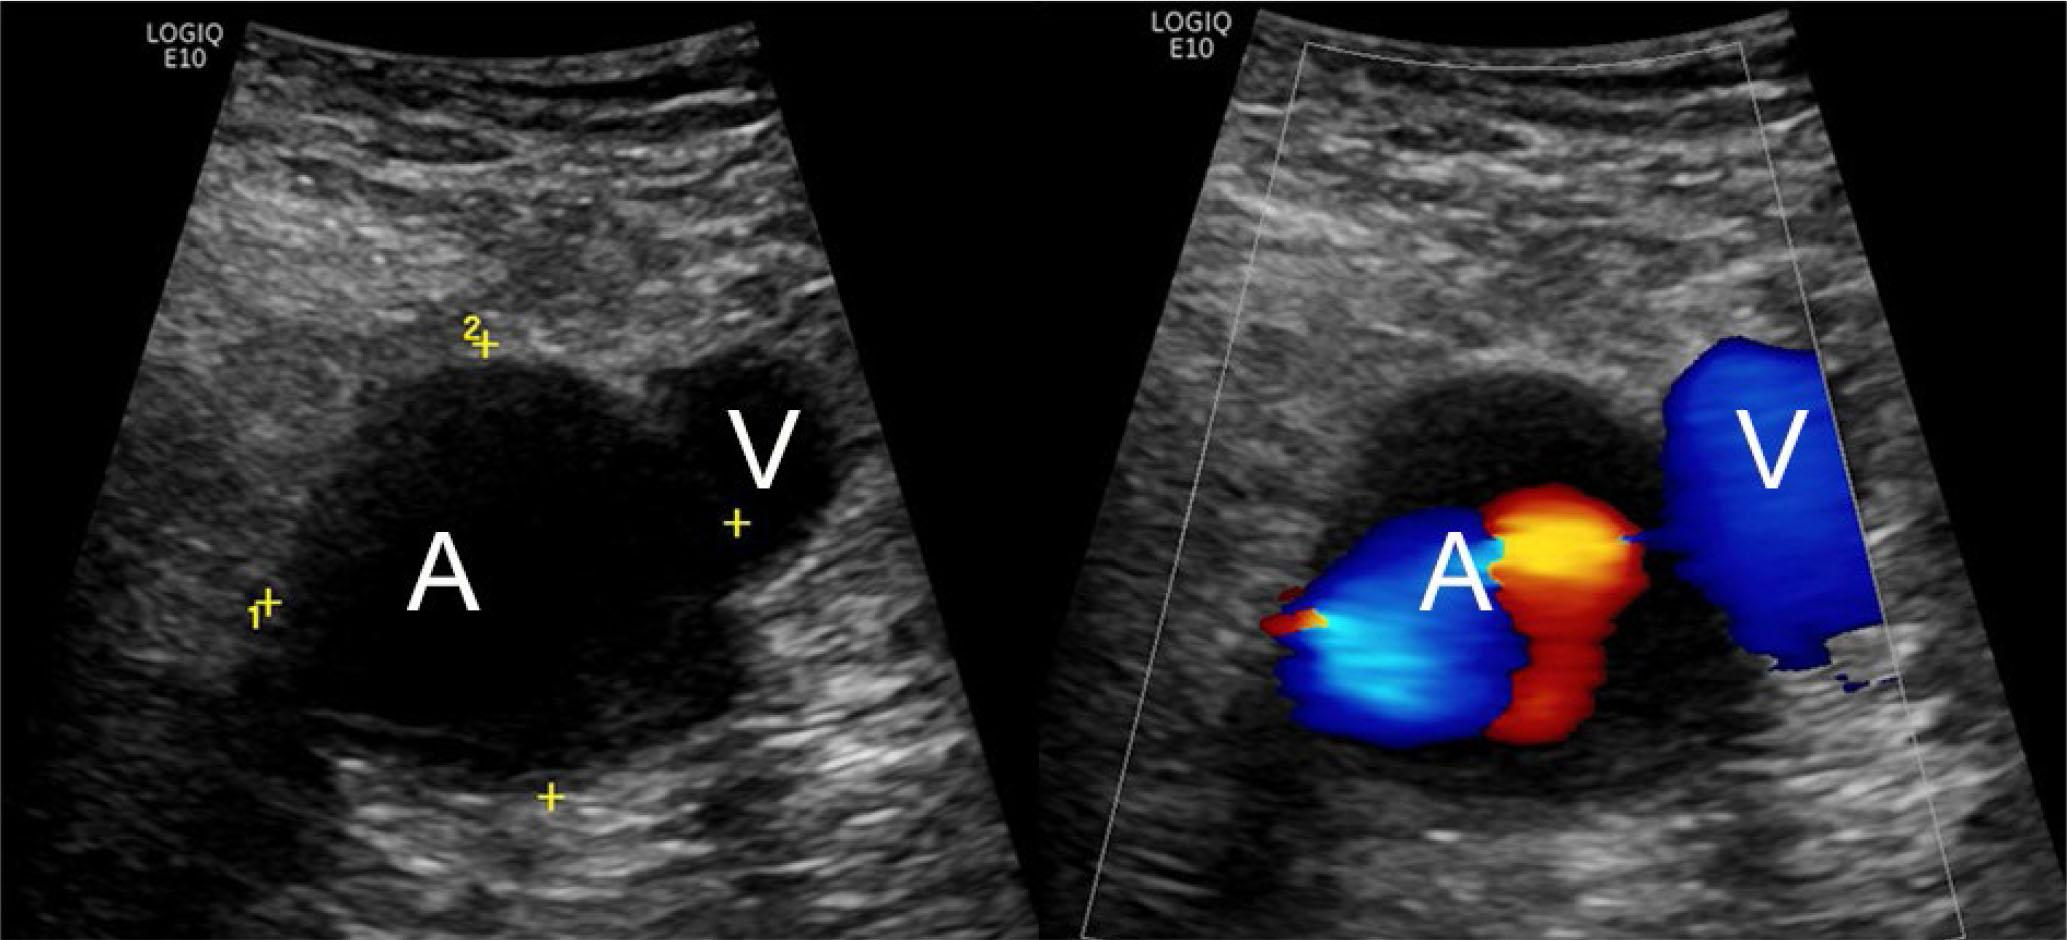

Solid masses identified on US or non-contrast enhanced MRI frequently require further characterization with contrast-enhanced MRI. Any cystic-appearing mass without clear joint contiguity or definite origin on MRI should be viewed with suspicion until a synovial sarcoma is excluded. Popliteal arterial aneurysms and pseudoaneurysms are readily identified by association with the popliteal artery on MRI and US, as well as internal flow at Doppler US (Fig. 19). Any mass that demonstrates deep intraarticular or osseous contiguity will be more completely assessed with MRI.

Fig. 19.

69-year-old male with popliteal artery aneurysm. Transverse grayscale and color Doppler US images show enlarged popliteal artery (A) adjacent to the normal vein (V) with internal turbulent flow